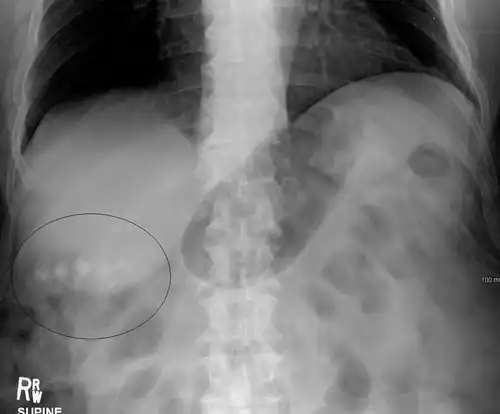

Diagnosis is typically confirmed by abdominal ultrasound. Other imaging techniques used are ERCP and MRCP. Gallstone complications may be detected on blood tests.[2]

On abdominal ultrasound, sinking gallstones usually have posterior acoustic shadowing. In floating gallstones, reverberation echoes (or comet-tail artifact) is seen instead in a clinical condition called adenomyomatosis. Another sign is wall-echo-shadow (WES) triad (or double-arc shadow) which is also characteristic of gallstones.[43]

Gallstones as seen on plain X-ray